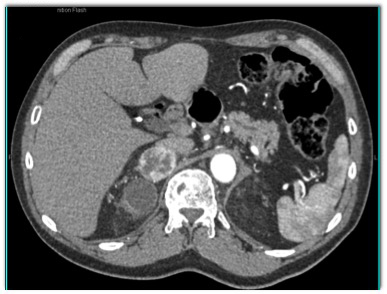

The best diagnosis for this incidental adrenal mass in a 65 yr. old male is?

CTisus Quiz   CTisus Quiz

adrenal adenoma

metastatic renal cell carcinoma

pheochromocytoma

adrenal hematoma